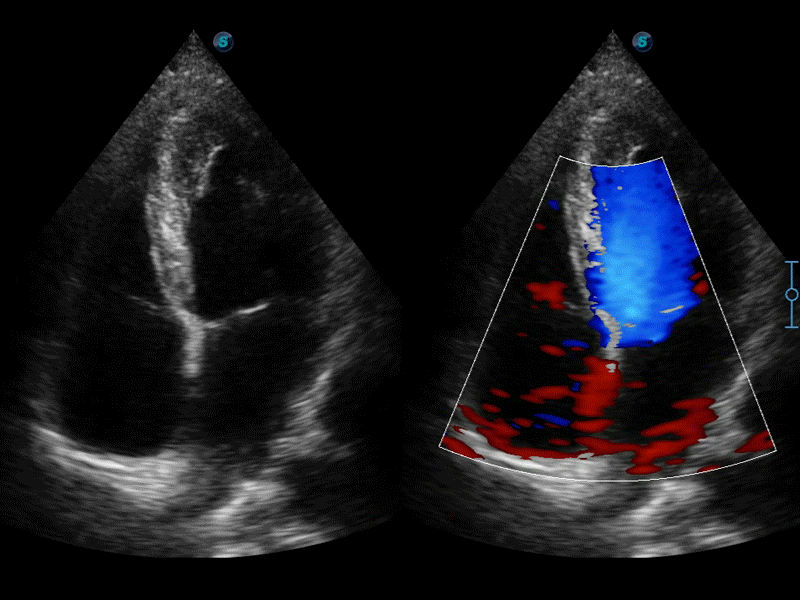

高分辨率血流成像技术提高了对低速血流信号的检测能力。在提高空间分辨率的同时,也克服了血流外溢现象,为用户提供更加真实的血流动力学信息。

通过色彩血流和实时宽景相结合,可观察到完整的静脉或动脉的血流,方便医生检查。实时扫查过程中,如有任何操作失误也可以很容易地进行回扫擦除,而不会中断扫查。